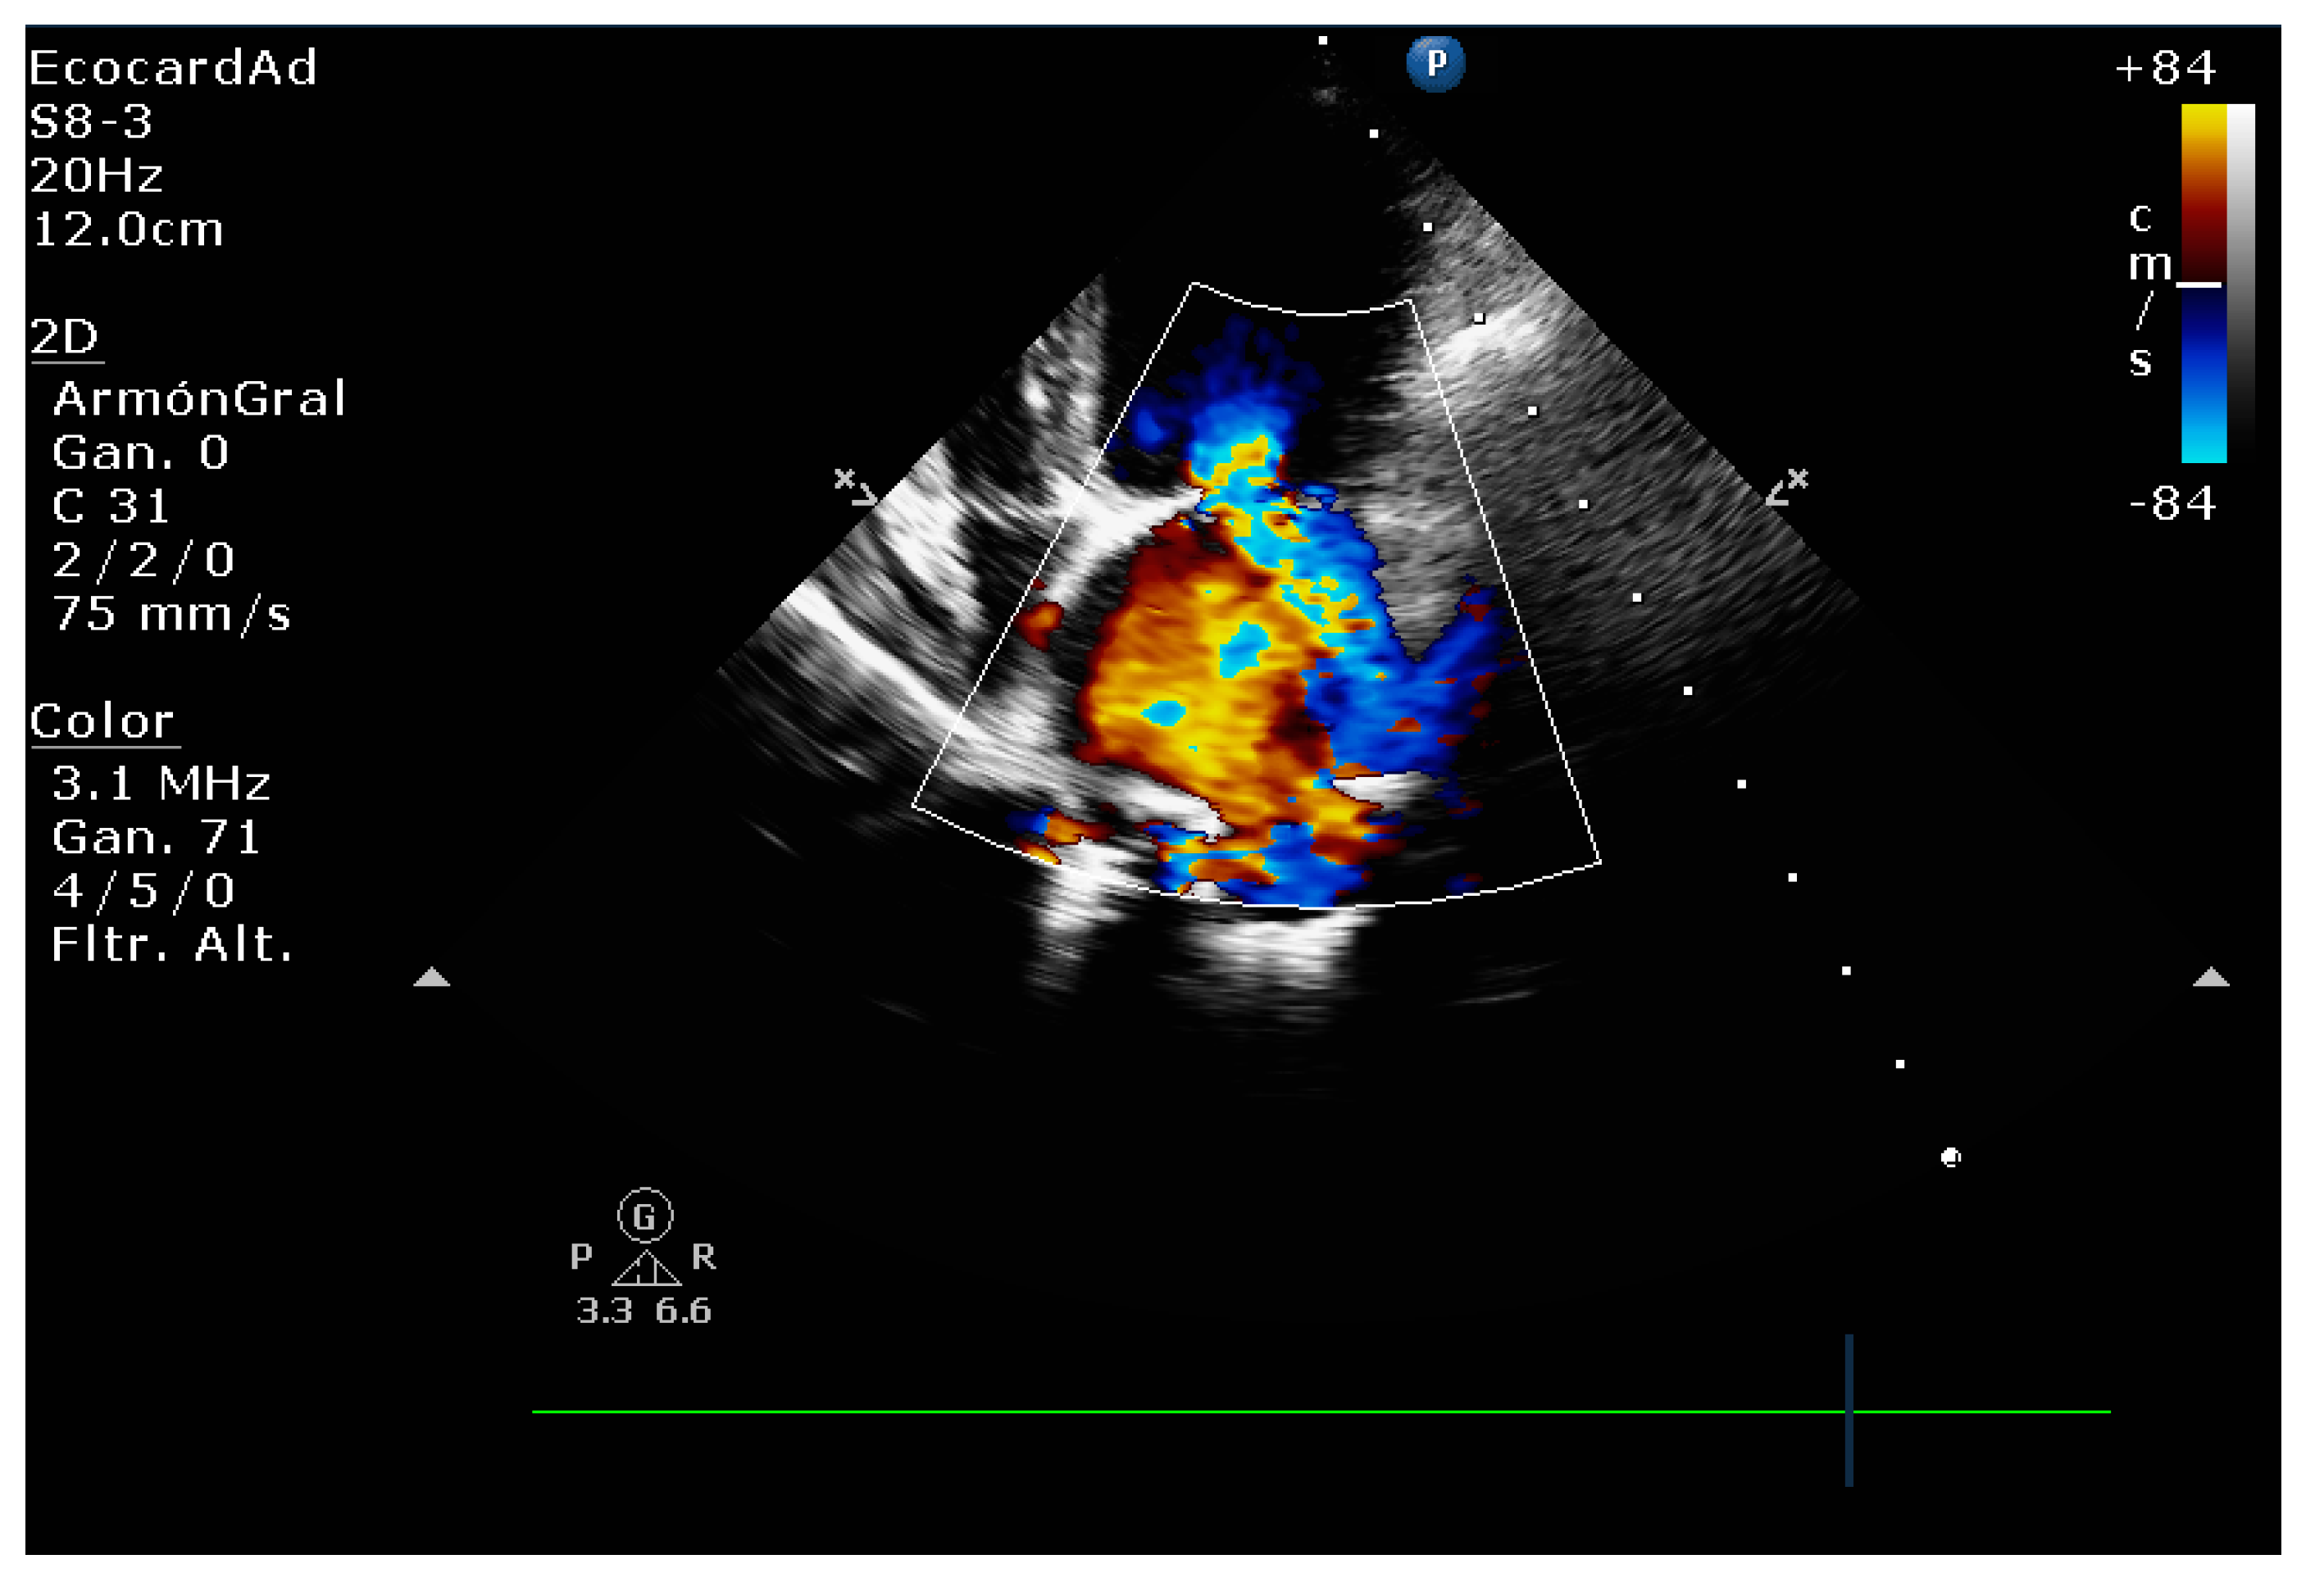

4.8.1. Evaluation of the Regurgitant Area

4.8.2. Presence of Vena Contracta

| Color flow imaging of the mitral regurgitation jet area | The most commonly used technique for assessing severity in dogs. The former method is not used in humans as it is not considered reliable for determining the severity of mitral insufficiency. |